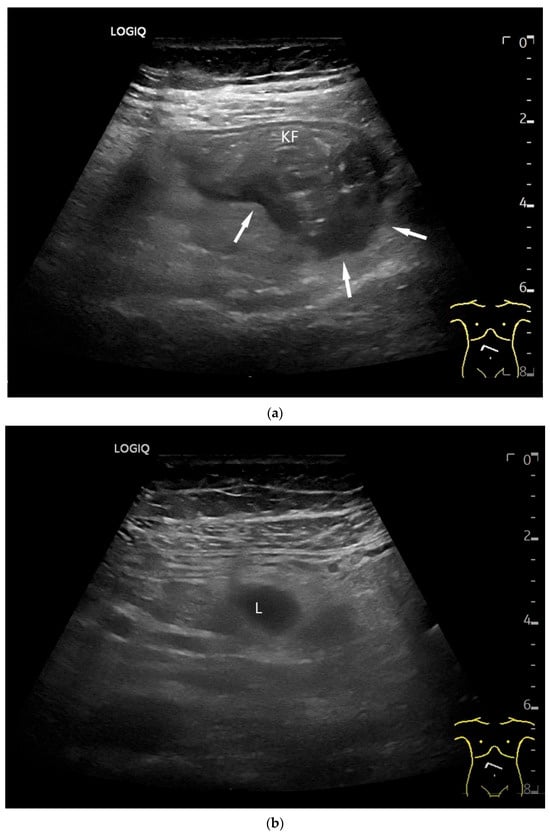

Adenocarcinoma in the duodenum. Significant hypoechoic wall thickening (between the markers) with narrowed lumen reflexes (a). The tumor has a slightly polycyclic border on the outside (a,b). Several tumor-suspicious, round, hypoechoic lymph nodes (L) are visible in the paraduodenal region (b).

Figure 6.

Jejunal Adenocarcinoma. Segmental hypoechoic wall thickening (arrows) in the jejunum discovered during anemia diagnostics. Kerckring folds are faintly visible (KF) (a). Adjacent to this is a large round hypoechoic lymph node (L). The surrounding area shows hyperechoic changes (b).